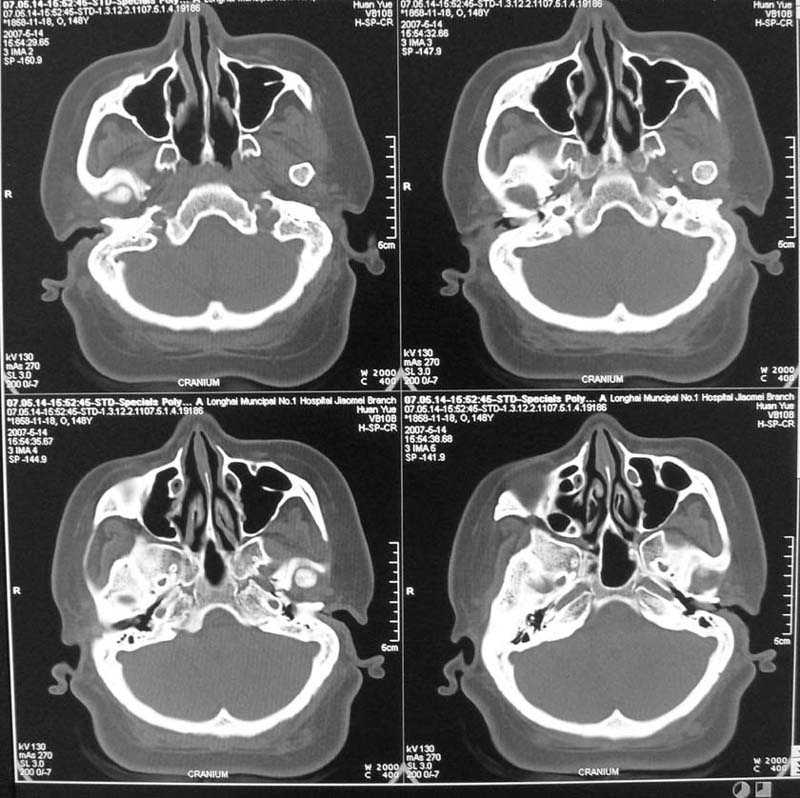

以下是引用天南地北在2007-5-15 23:30:00的发言:[br]看不出来什么[br]建议冠面增强扫描,或mri检查

以下是引用郭凯在2007-5-16 0:17:00的发言:[br]看不到,如果临床支持的话还是做mri看一下吧,对垂体微腺瘤比较敏感.[br]ct上看不到不能乱报.

以下是引用jiangjing在2007-5-16 11:06:00的发言:[br]看不出来什么[br]建议冠面增强扫描,或mri检查